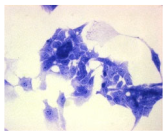

| Control | Doxycycline (DOX) | DOX + C1 | DOX + C2 | |

|---|---|---|---|---|

| SH-SY5Y cells | ||||

| May–Grunwald staining | ![]() | ![]() | ![]() | ![]() |

| HepG2 cells | ||||

| HEK-293 cells | ||||